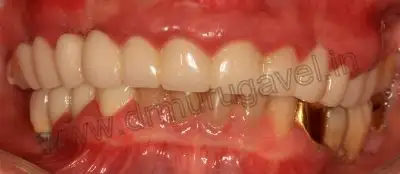

Pre-op front view

post-op front view